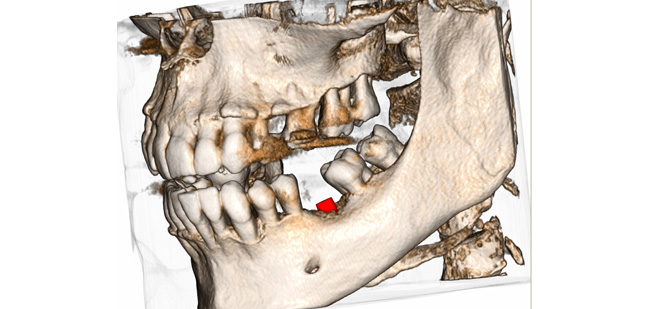

Endo-Perio

Der Facharzt für Endodontie und Periodontologie benötigt Bilder von absoluter Spitzenqualität und Detailschärfe, um Verfahren wie die Behandlung von Zahnbrüchen, die Heilung von Zahngewebe und die Therapie des Kieferkanals vorzunehmen, da er über genaue Details der behandelten Zone und des Krankheitsbilds verfügen muss, um eine wirkungsvolle Behandlung planen zu können. Nur eine eingehende Untersuchung der betroffenen Areale kann Aufschluss über einen mehr oder weniger invasiven Eingriff geben.